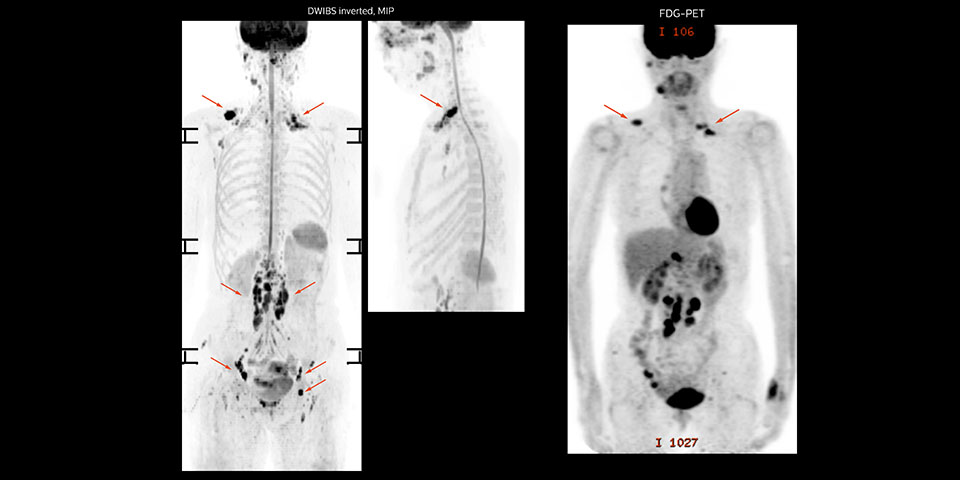

Whole body diffusion

A 61-year-old female with a malignant lymphoma underwent an MRI exam with whole body diffusion weighted imaging (DWIBS) as well as PET. On the images shown, the resolution of DWIBS is better than PET, which allows visualization of the small pelvic lesions and almost no distortion is seen in the neck area.

Prodiva MRI whole body DWI lymphoma, Seirei Mikatahara

Prodiva MRI whole body FDG-PET, Seirei Mikatahara